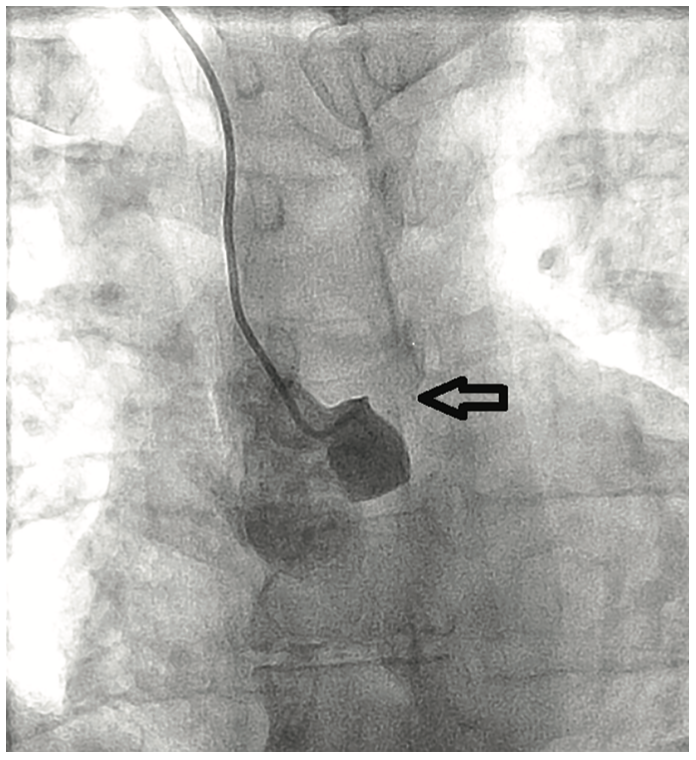

Angiographic findings of atherosclerotic disease and stenosis in the left main coronary artery are not uncommon in both symptomatic and relatively asymptomatic patients. However, the angiographic finding of a completely occluded left main coronary artery is relatively uncommon and most often not compatible with life.1,2 It is even more unusual to have no symptoms related to the complete obstruction of the left main coronary artery.

Left main coronary artery stenosis to a varying degree is not an uncommon finding on coronary angiography in patients with known and unknown coronary artery disease. Several reports and studies have been published pertaining to clinical presentation and management of left main coronary artery stenosis, but very little is known about the clinical presentation or incidence of left main coronary artery occlusion. This is likely due to total occlusion of the left main coronary artery being incompatible with life. Total occlusion of the left main coronary artery is usually a highly symptomatic event or in many cases, a terminal event. The survival rate and clinical symptoms are likely correlated with the rate of occlusion and the degree of collateralization from the right coronary artery that can supply blood flow to the left coronary arteries when the left main coronary artery becomes totally occluded.